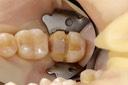

Kyle Chock #2 caries removal